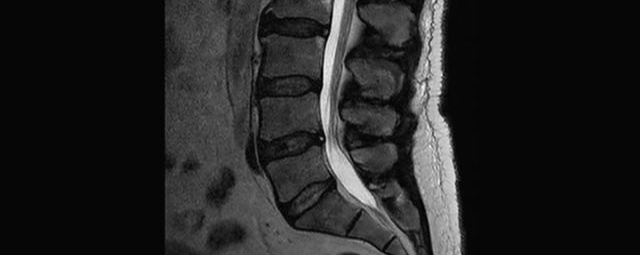

- Abklärung Bandscheibenvorfall

- Beurteilung Einengung des Rückenmarkkanals oder der Neuroforamina im Rahmen der degenerativen Wirbelsäulenerkrankung

- Tumor-/Entzündungsdiagnostik

- Abklärung Spondylolisthesis

- Frakturdiagnostik (Alter und Ausdehnung der Fraktur) z.B. im Rahmen der Osteoporose